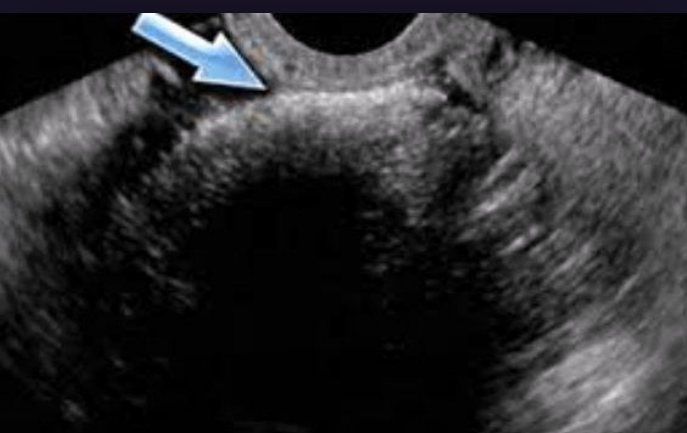

What type of fibroid is depicted in this image?

A. Intramural

B. Submucosal

C. Subserosal

D. Pedunculated

Subserosal